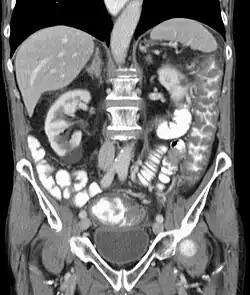

Pseudomembranous colitis on computed tomography

Before the advent of tests to detect C. difficile toxins, the diagnosis most often was made by colonoscopy or sigmoidoscopy. The appearance of "pseudomembranes" on the mucosa of the colon or rectum is highly suggestive, but not diagnostic of the condition.[46] The pseudomembranes are composed of an exudate made of inflammatory debris, white blood cells. Although colonoscopy and sigmoidoscopy are still employed, now stool testing for the presence of C. difficile toxins is frequently the first-line diagnostic approach. Usually, only two toxins are tested for—toxin A and toxin B—but the organism produces several others. This test is not 100% accurate, with a considerable false-negative rate even with repeat testing.[47]